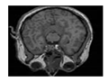

This section contains extensive performance evaluation findings for the three suggested approaches. The developed systems were tested over Matlab environment. As shown in Figure 6, the suggested encryption techniques have been tested for color, grayscale, and medical photos, each of which is 256 × 256 pixels in size, with watermarks of 64 × 64 pixels.

Figure 6.

Color, grayscale and medical images and watermarks.